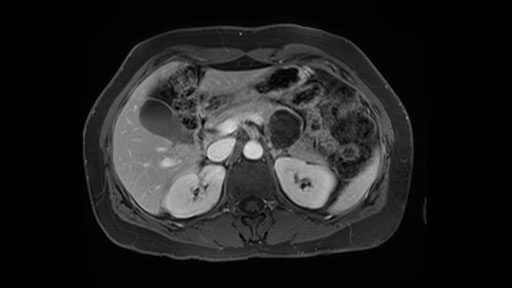

The slowing down moments or considerations that I give when I look at the scan and plan my distal pancreatectomy is how far away the tumor is to the portal vein and do I have to formally create a tunnel behind the pancreas on top of the portal vein or do I have to take the pancreas further to the left of the portal vein or the patient’s left of the portal vein. So here I can see that here is the tumor here. I can see that the tumor is a fair way away to the patient’s right and so I will likely not have to take or create the tunnel formally in this procedure. And that speaks a lot to the resection margins. So its important when you’re doing a distal pancreatectomy or any procedure potentially for oncologic reasons to get clearance of the tumor and to take the tumor kind of intact.

The second slowing down moment or consideration I give to a distal pancreatectomy is the anatomy of the portal vein and the splenic artery. And so I look here and the anatomy is pretty straightforward. The splenic vein comes off normally and runs behind the pancreas and I can see the artery superior to that, again coming off in a normal manner from the celiac axis. So those two things, the portal vein and the splenic artery will be taken normally in this procedure.

Key features that I look at the imaging are: first I look at the distance between the cyst and the portal vein SMV confluence. So there are guidelines for this, they call the Yonsei guidelines, to decide to do it laparoscopically or open and basically it says that if it’s a cancer, at least a centimeter away from the celiac trunk or the venous confluence. This is a cyst. So maybe you could stretch that a bit, but you don't want to get into trouble there. So for this cyst if you look at it, it's nicely away from the confluence.

So unfortunately I cannot show you a coronal view but you can see it easily on this scan, going down first you see the celiac trunk and you see here, quite a nice distance between the celiac trunk and the beginning of the mucinous cyst. And if you go up here and follow down the portal vein confluence you also see a nice distance there.

So what I would normally do in these patients, I would look at the abutment of any other organs, one, which is here, potentially the adrenal gland and two the small bowel. And two, look at the distance from the vessels which I would normally do in a coronal view. So you can easily measure the distance and third I look at the insertion of the inferior mesenteric vein. Now we can probably also see that on here. Although it's better on a CT scan and it's better on a coronal view, you want to know where the inferior mesenteric vein comes into either the splenic or the SMV, because that is typically a very important slow down moment when you mobilize the lower portion of the pancreas knowing where the inferior mesenteric vein comes in either the splenic vein or the SMV. So those are I think the three most important points for the CT scan.